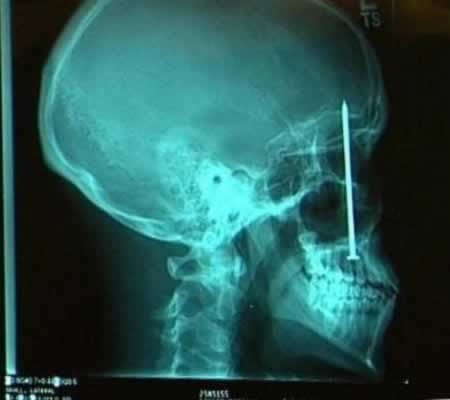

دوست این پسر بچه 11 ساله چینی یک میله 16 اینچی رو به سمت سر این بچه پرتاب می کنه و میله از حدقه چشم وارد جمجمه میشه و در انتهای جمجمه جا خشک می کنه ولی به مغزش آسیب کشنده ای نمی رسه!!!!!!

این آقای کره ای میره دکتر و از سر دردش شکایت می کنه.بعد دکترها متوجه می شند یک میخ 5 سانتیمتری 4 سال پیش در اثر یک تصادف وارد جمجمه این آقا شده و ایشون نمی دونستند!!!!!